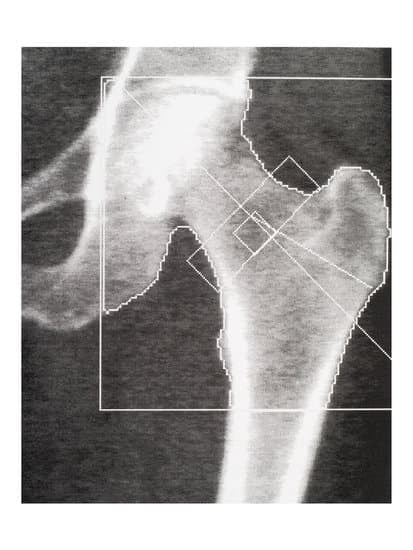

골밀도 검사에는 여러 가지 방법이 있지만, 가장 정확하고 널리 사용되는 방법은 이중 에너지 X선 흡수계측법(DXA, Dual-energy X-ray Absorptiometry) 입니다.

(1) DXA 검사 (이중 에너지 X선 흡수계측법) - 가장 일반적인 방법

✅ 검사 부위: 척추(허리뼈), 대퇴골(엉덩이뼈)

✅ 검사 시간: 약 10~20분

✅ 방사선 노출: 매우 적음 (일반 엑스레이보다 낮음)

✅ 정확성: 높은 정확도로 골밀도를 측정하여 골다공증 진단에 가장 많이 사용됨